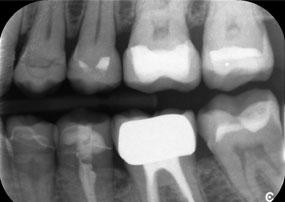

A x-ray, showing teeth and a zirconia crown, in front of a black background.

Figure 2: Replacement of a damaged zirconia crown: Precise removal and renewal of a damaged zirconia crown on tooth 6 with minimal material loss.